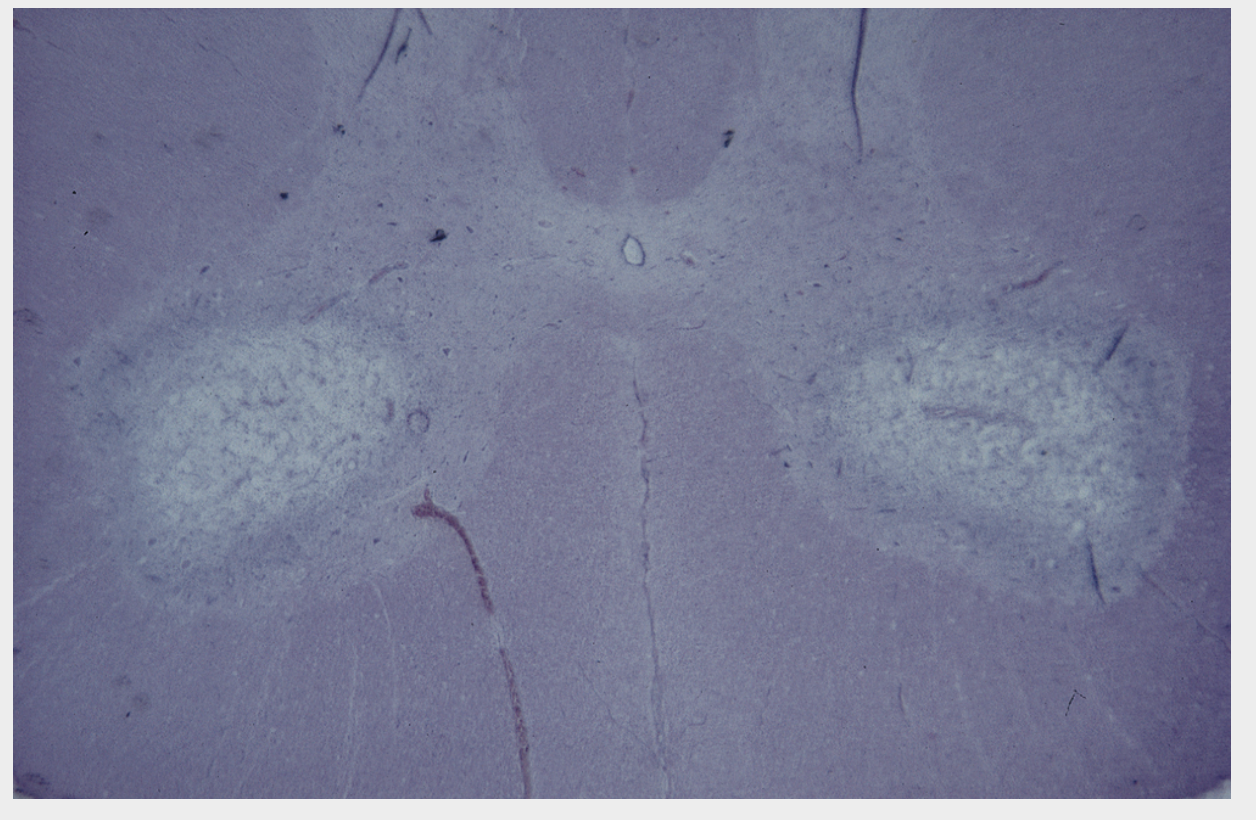

See image, most likely dx? SC of a pig

Selenium poisoning (poliomyelomalacia) There is bilaterally symmetrical loss of staining in the ventral horns of the cervical intumescence due to poliomyelomalacia. Microscopically, initial lesions include neuropil vacuolation, necrosis of glial cells, capillary hypertrophy and neuronal degeneration. In the chronic stage, the picture is predominated by neuronal loss and extensive gliosis with capillary proliferation in the ventral horns. In addition, many brainstem nuclei and cerebellar roof nuclei may be similarly affected.